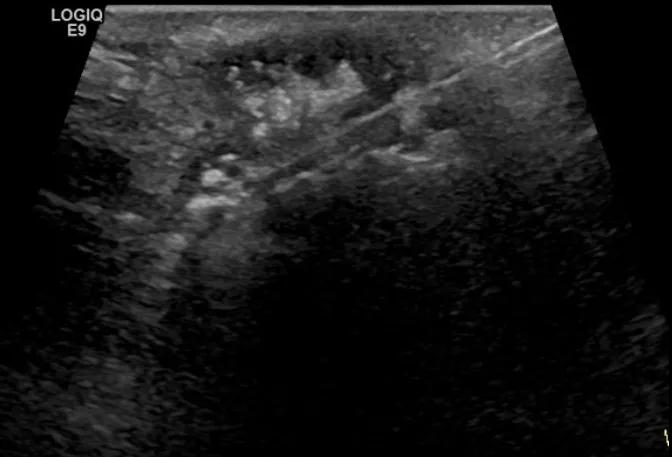

第四例是胸腺癌化妆包,术后、化疗之后淋巴结转移,肿块范围巨大,99mm*61mm,边界不清,呈浸润状,肿块包绕颈动脉,颈内静脉压闭,症状明显。由于患者放化疗也不敏感、血供非常丰富,于是采取多点姑息性消融。姑息性消融后未实现完全消融,病灶大片坏死,肿胀疼痛得到明显的缓解,后续患者未再来复查。

(病例4图例)